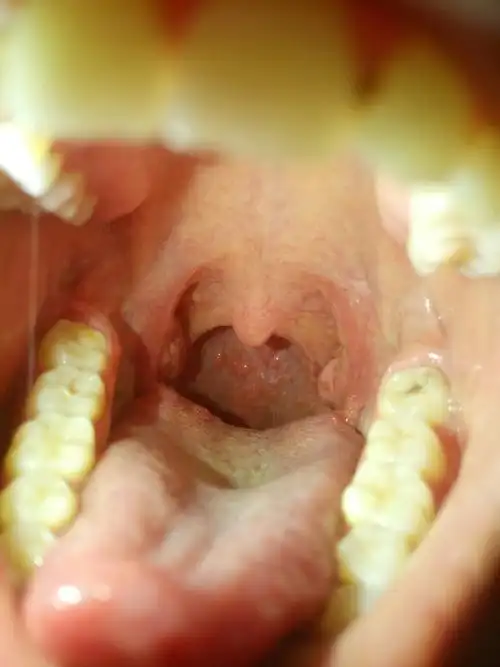

有儿子的妈嗓子永远是疼的

孩子喉咙不舒服老清嗓子,孩子喉咙不舒服是什么原因?

喉咙严重上火还有泡一个多月了还没有好,现在声音也

声带长息肉让嗓子嘶哑失声